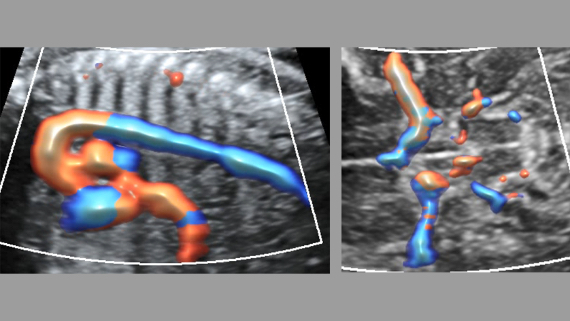

ImĂĄgenes clĂnicas